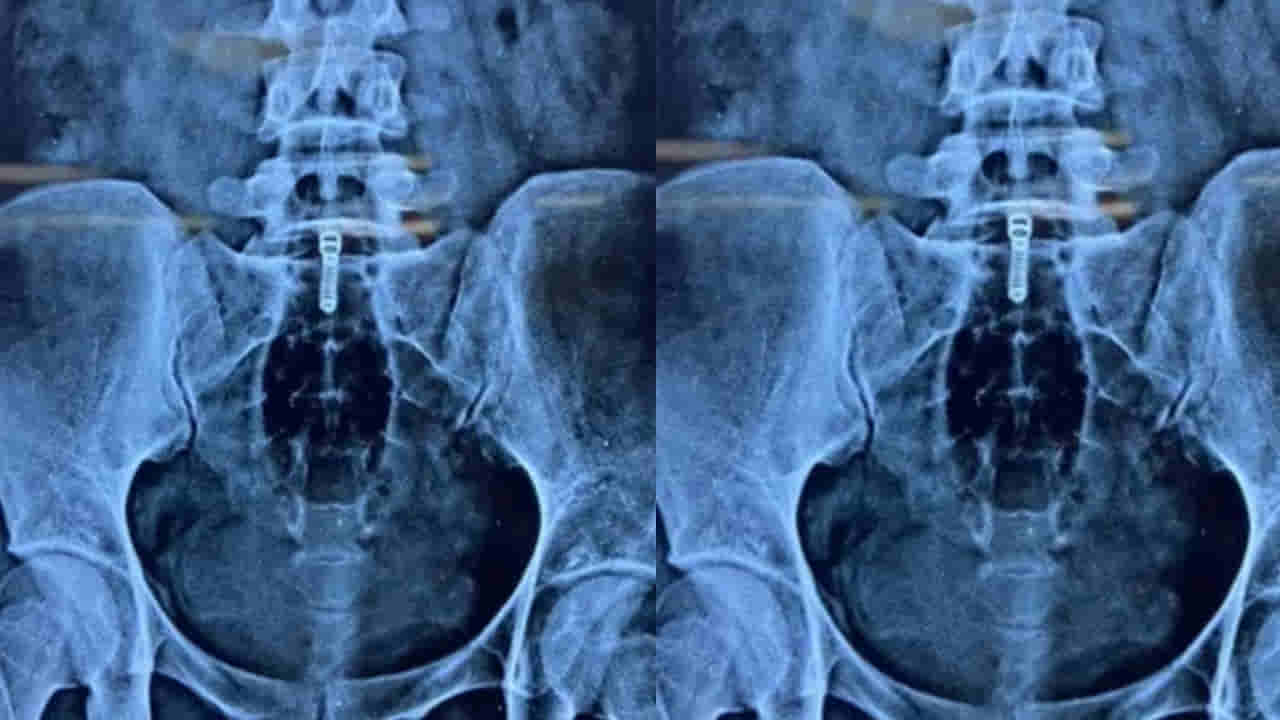

ముందుగా ఆమె ఓ స్థానిక ఆసుపత్రిని సంప్రదించినా… అక్కడ చికిత్స విఫలమైంది. ఆపై తీసిన ఎక్స్రే స్కాన్లో బాటిల్ పై భాగంలో ఉన్న రెక్టల్ ప్రాంతంలో ఉన్నట్లు గుర్తించారు. ఆ స్థితిలో ఆపరేషన్ తప్పనిసరి అయిపోయిన వేళ.. నిపుణుల బృందం రంగంలోకి దిగింది. డాక్టర్లైన తరణ్ మిట్టల్, ఆశిష్ డే, అన్మోల్ అహుజా, శ్రేయస్ మంగళిక్, అనస్తటిస్ట్ ప్రశాంత్ అగర్వాల్ నేతృత్వంలో అత్యంత జాగ్రత్తగా సిగ్మాయిడోస్కోపీ పద్ధతిలో బాటిల్ను తొలగించారు. శరీరాన్ని కోయకుండా చేసిన ఈ ప్రక్రియ వల్ల బాధితురాలు వేగంగా కోలుకుంది